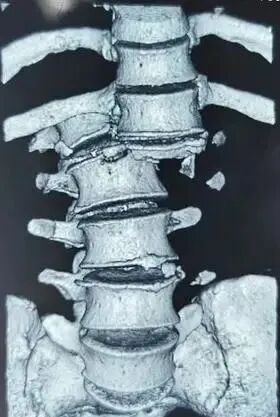

最常见的情况之一是脊柱后脱位。

面部、前额和脸颊遭受暴力和意外时,可能会导致脊柱过度拉伸。一旦暴力超过了颈前肌肉群体和前纵韧带的张力,脊柱就会过度拉伸。

此时,身体处于相对稳定的状态,颈部七个椎体以下的部位不会随着颈椎的活动而移动,因此就会在脊柱上形成水平切力,导致韧带撕裂,情况更为严重时,就会发生脊椎后脱位现象。